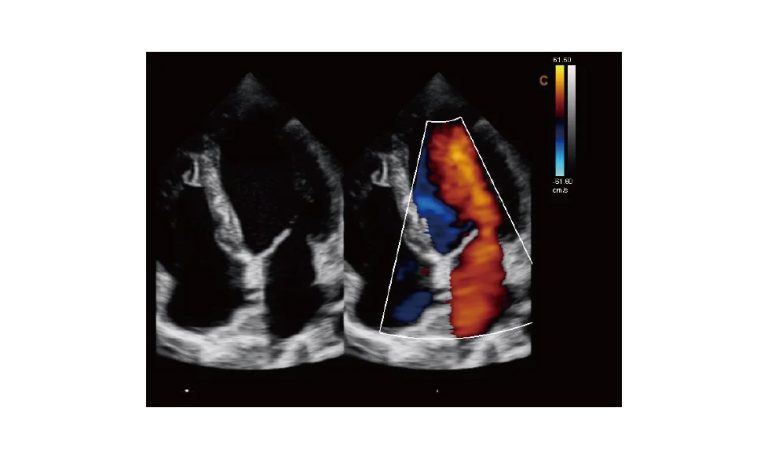

Ultrasound

Wide range of Ultrasound machines that suites a variety of applications from abdominal to rectal scans, we take in consideration how the world is moving towards mobility and mobile applications.

SonoScape Pro Pet E11

Smart Imaging

Introducing the first portable ultrasound with the C-Field+TM platform, redefining diagnostic imaging. Designed for veterinarians, it delivers unmatched clarity, ultra-fast processing, and seamless adaptability for all species. Experience Smart Imaging, Heartfelt Care—anywhere.

Equipped with cutting-edge veterinary software and optimized workflows, it embodies our commitment to Smart Imaging, Heartfelt Care – Wherever Their Journey Leads, with unparalleled performance and adaptability, this innovative system empowers veterinarians to provide exceptional care across all diagnostic applications,

EBIT50/60 VET

All the power you need

The EBit provides all the power you need for today´s challenging clinical environment, yet remain ultra-portable, ultra-affordable. With its cutting-edge imaging technologies, precise and intuitive workflow, ergonomic and eco-friendly design, versatile transducers for all applications from top to toe, we firmly believe the EBit to be the very best portable ultrasound in its class today.

ECO5 VET

Ultra-Portable, Ultra- Affordable, Color doppler

The multi-purpose user presets, comprehensive measurement & report system, built-in EasyView image achieve system, quick image storage / retrieve / transfer, one-button direct print, make the complete workflow better than what you can dream of.